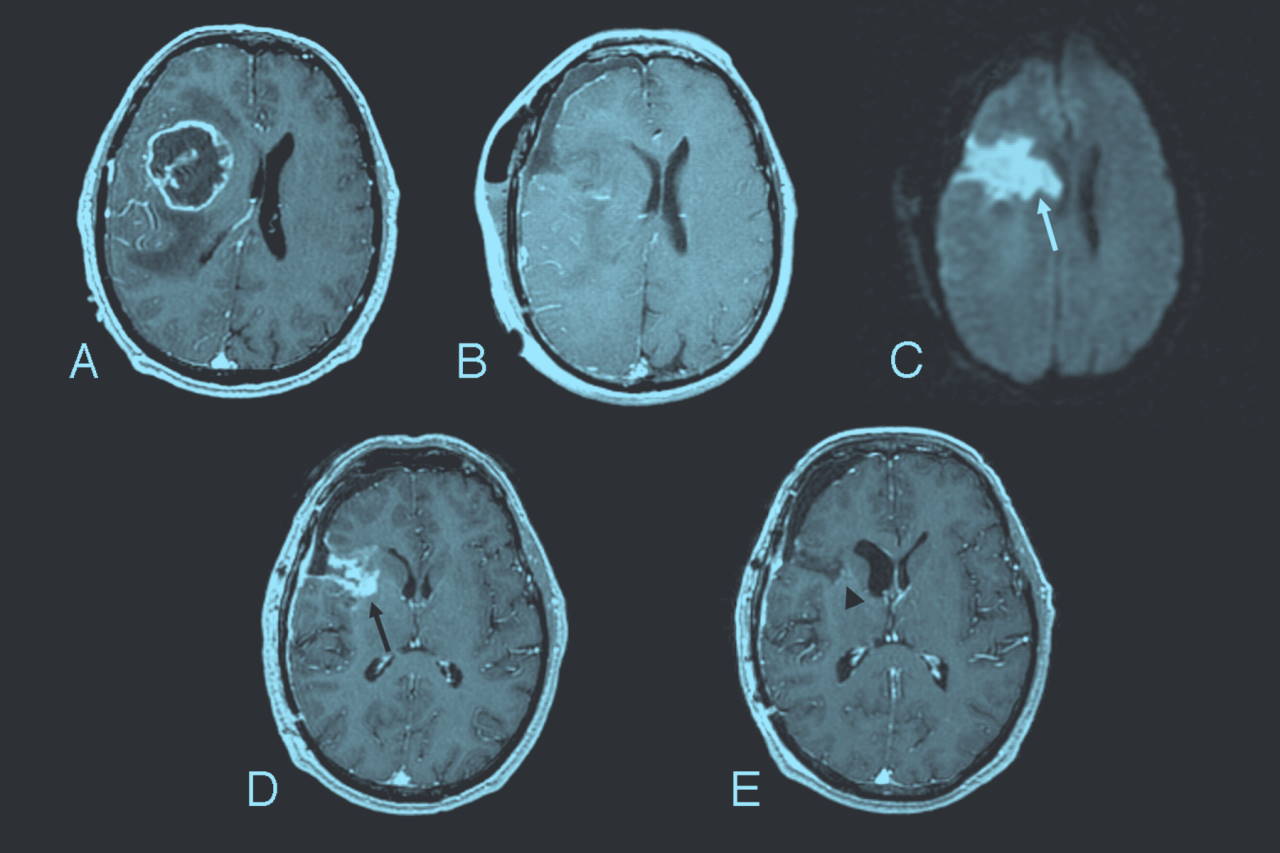

Рак мозга процент

Рак мозга процент 109 фотографий